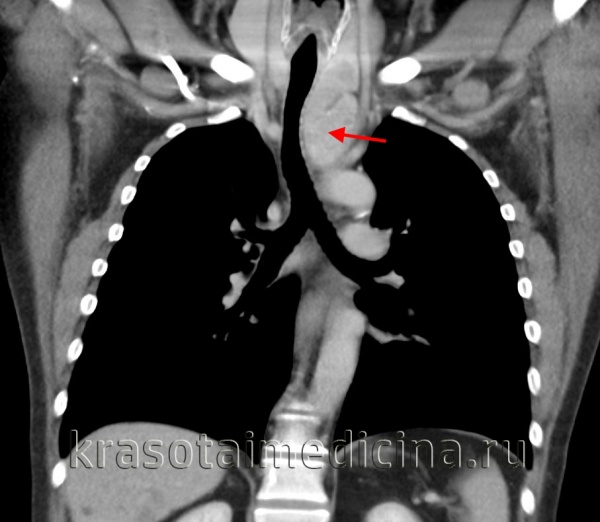

Больная П., 38 лет, поступила 31/VIII 1994 г. с диагнозом: опухоль средостения. Жалобы на тупые боли и чувство онемения в левой половине грудной клетки, одышку, слабость, повышенную потливость. Больна в течение года, симптомы болезни усиливаются.

При обследовании в клинике со стороны сердечно-сосудистой системы легких отклонений не найдено. На рентгенограммах видна овальной формы тень, расположенная справа в передневерхнем средостении. После искусственного пневмоторакса установлена интактность легкого. Заключение: киста передневерхнего средостения.

6/Х операция. Под местной анестезией передним доступом через третье межреберье справа вскрыта плевральная полость. В передневерхнем отделе средостения обнаружена опухоль размером 12 х 10 см, мягко-эластической консистенции, спаянная с верхней полой и непарной венами. При мобилизации опухоли вскрыта ее полость, из которой удалено около 100 мл жидкости, имевшей вид молока. Опухоль с капсулой удалена. Послеоперационное течение гладкое.

Гистологическое исследование показало налииче кистозной лимфангиомы. Видна стенка кисты, состоящая из волокнистой соединительной ткани, сосуды полнокровны. Определяются лимфатические фолликулы, мелкие лимфатические узелки, участки жировой ткани.